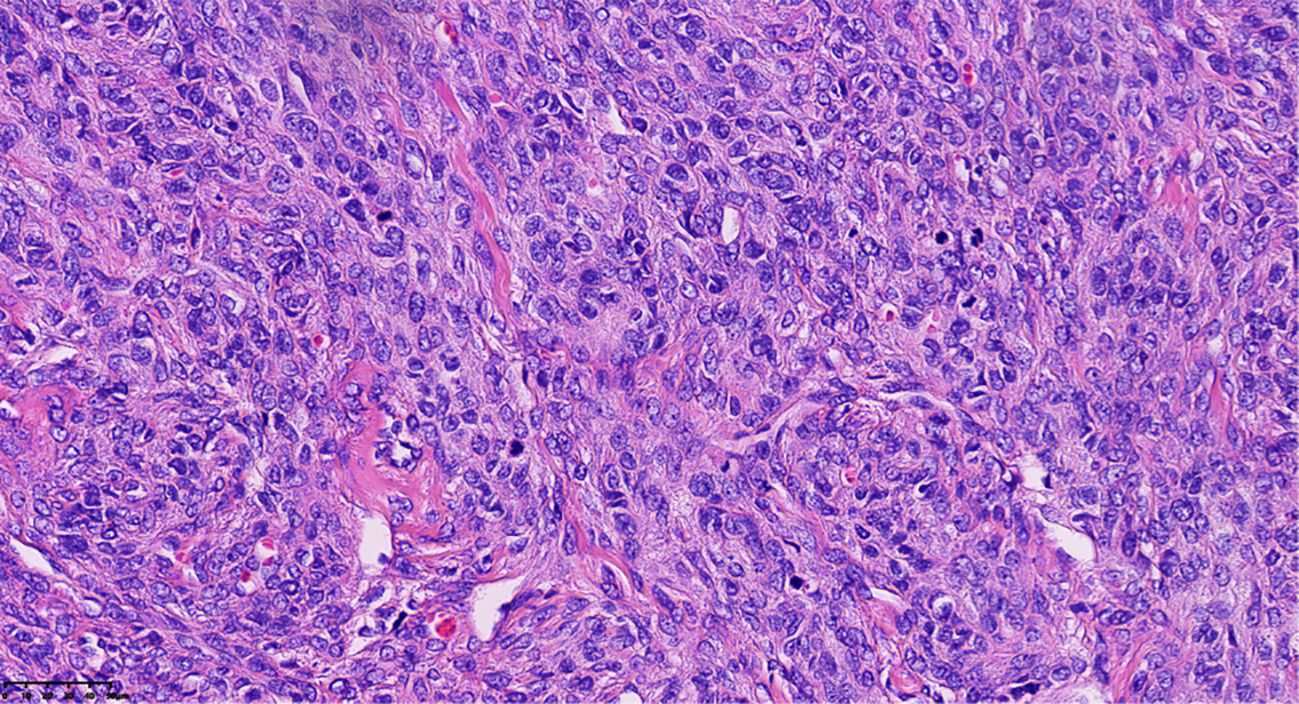

Final histopathological examination revealed a densely cellular spindle cell tumor. Mitotic figures were counted in the areas of highest cellularity (“hot spots”) across 10 consecutive HPFs using a 40x objective (ZEISS™/Lab.A1, field area 0.237 mm²), revealing a pronounced mitotic rate of approximately 15/10 HPF (equivalent to 6–7 mitoses/mm²). Foci of moderate cytological atypia were present; however, diffuse severe atypia, atypical mitoses, and tumor necrosis were explicitly sought and found to be absent (Figure 3). These features, together with the clinical course, supported MACF rather than fibrosarcoma despite the brisk mitotic activity. Immunohistochemical (IHC) staining showed tumor cell positivity for Vimentin (Vim) (confirming mesenchymal origin) and CD99, with focal expression of Smooth Muscle Actin (SMA) and the sex-cord stromal markers α-inhibin and calretinin. Staining was negative for Desmin and Caldesmon (ruling out smooth muscle origin), Cytokeratin 7 (CK7) and Epithelial Membrane Antigen (EMA) (ruling out epithelial origin), and the germ cell tumor markers Wilms Tumor 1 (WT1), Spalt-like transcription factor 4 (SALL4), and Octamer-binding transcription factor 4 (OCT4). This immunoprofile was most consistent with a sex cord-stromal tumor of fibroblastic type. The Ki-67 labeling index was markedly elevated at approximately 60%.

Pathological clues of tumor cells revealed densely cellular spindle cell tumor areas, with foci of moderate cytological atypia and pronounced mitotic activity, approximately 15/10 HPF (Hematoxylin and eosin stain; magnification, ×40).